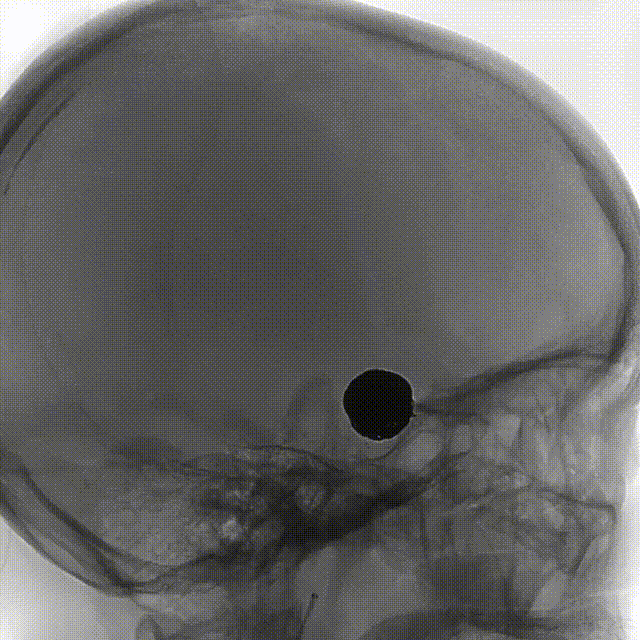

完全释放FRED 4017血流导向密网支架辅助弹簧圈栓塞后,正、侧位及3D造影观察,载瘤动脉通畅、支架贴壁良好、动脉瘤内造影剂滞留。

4个月后随访DSA,右侧颈内动脉正、侧位造影可见瘤颈缺损处内皮化修复,动脉瘤治愈。